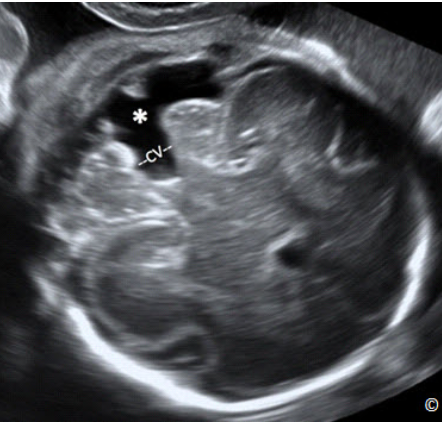

Figure 5.1: A transverse plane of the fetal head at the level of the biparietal diameter (BPD). In this

plane, you should see the cavum septae pellucidi (CSP), the falx (labeled), the thalami (T), 3rd

ventricle (3V) and the insula (labeled). A portion of the lateral ventricle is also seen (labeled).

Hình 5.1: Mặt cắt ngang của đầu ở đường kính lưỡng đỉnh. Ở mặt cắt này cho thấy vách trong suốt

(CSP), liềm não (Falx), đồi thị (T), não thất ba (3V), thùy đảo (insula) Một phần của não thất bên cũng

đươc ghi nhận ở mặt cắt này (Lateral V).

Three axial sonographic planes are needed to assess the head anatomy: the plane at the level of

the lateral ventricles (Figure 5.11), the plane at the level of the BPD (Figure 5.2), and the plane

at the level of the posterior fossa (Figure 5.12).

3 mặt cắt ngang trên siêu âm cần dùng để đánh giá giải phẫu học vùng đầu: mặt cắt

ngang não thất bên (

hình 5.11), mặt cắt ngang đường kính lưỡng đỉnh (Hình 5.2), và

mặt cắt ngang hố sau (

hình 5.12)

Figure 5.11: Transverse plane of the fetal head at the level of the lateral ventricles

(LV). Sonographic landmarks for LV measurement include the LV, the cavum septae

pellucidi and the midline falx (labeled). The LV is measured at the level of the atrium

(asterisks). CP = Choroid Plexus.

Hình 5.11: Mặt cắt ngang đầu ỏ vị trí ngang não thất bên 2 bên (LV). Các mốc giải phẫu

của mặt cắt bao gồm não thất bên, vách trong suốt và liềm não (Falx). Não thất bên được

đo ở ngã ba của não thất (dấu sao). CP = Choroid Plexus: đám rối mạng mạch.

This represents an axial view of the fetal head, at the level of the lateral ventricles (Figure 5.11).

Sonographic landmarks identifying the correct anatomic plane include the lateral ventricles, the

cavum septae pellucidi and the midline falx (Figure 5.11). On this view, the width of the atrium

of the distal lateral ventricle should be measured (Figure 5.11). Visualization of the proximal

lateral ventricle is obscured by proximal parietal bone shadowing (Figure 5.11). The atrium of

the lateral ventricle should be measured at the level shown in Figure 5.11 and should be equal to

or <10.0 mm. anytime in gestation.